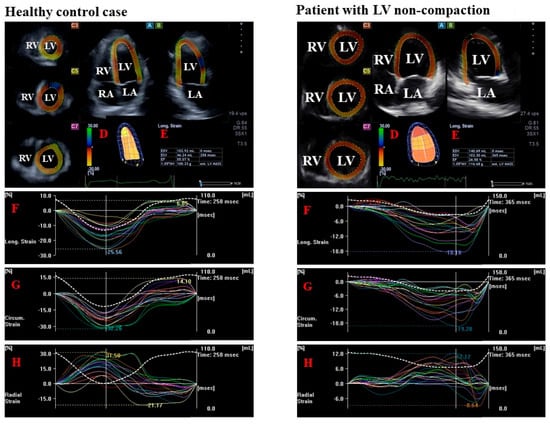

- LV radial strain (RS), which represents thickening/thinning of the LV.

- LV circumferential strain (CS), which represents narrowing/widening of the LV.

- LV longitudinal strain (LS), which represents shortening/lengthening of the LV.

| Basal LV-RS (%) | 31.8 ± 11.8 † | 27.6 ± 8.5 # ‡ | 35.2 ± 12.9 @ | 15.0 ± 8.0 | 15.4 ± 8.4 | 13.4 ± 7.6 |

| Basal LV-CS (%) | −26.1 ± 5.6 † | −27.2 ± 5.6 ‡ | −25.2 ± 5.4 @ | −10.2 ± 3.1 | −10.4 ± 3.3 | −8.6 ± 2.5 |

| Basal LV-LS (%) | −20.4 ± 4.4 † | −18.9 ± 3.5 # ‡ | −21.5 ± 4.6 @ | −9.1 ± 2.2 | −9.0 ± 2.3 | −8.7 ± 2.0 |